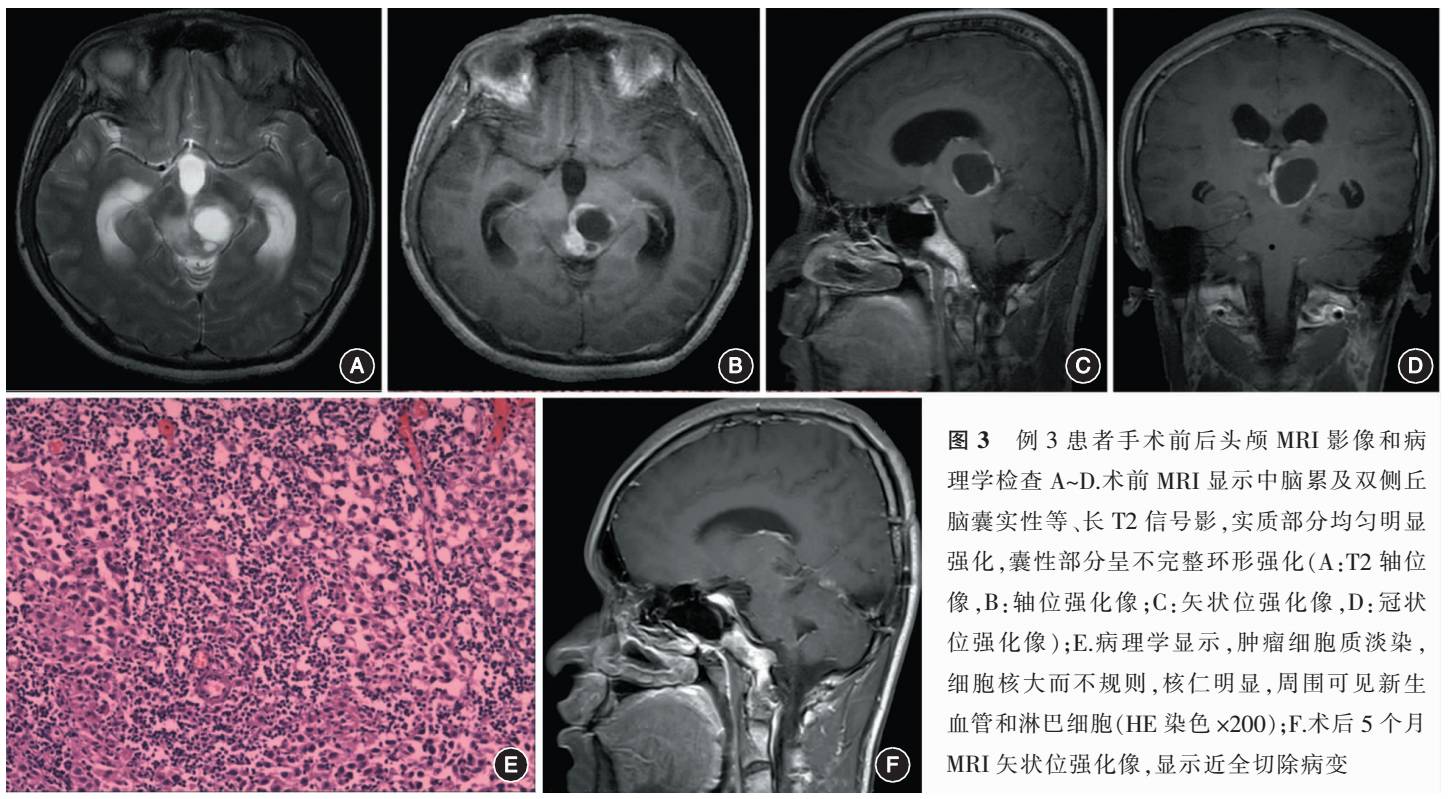

例1 女,19岁。因“走路不稳伴双手阵发性麻木1个月”于2016年2月入院。神经系统检查示,双侧共济运动差,双上肢浅感觉减退。头颅MRI平扫示脑干增粗,可见类圆形长T1、T2高低混杂信号影,增强后呈不规则均匀明显强化,向后突起,第四脑室受压变形(图1A~C),幕上脑室扩大,周围见长T1、长T2信号影。弥散加权成像(DWI)显示脑干后方病变呈低信号改变。术前诊断为“脑干胶质瘤”。行枕下后正中入路肿瘤切除术,术中见肿瘤位于脑桥背侧,突向第四脑室,质软,灰红色,与脑桥组织边界不清,沿脑桥后中线切开,近全切除病变(图1D~E)。病理学诊断为生殖细胞瘤(图1F),免疫组化显示胎盘碱性磷酸酶(placental alkaline phos-phatase,PLAP)、POU结构域转录因子(OCT3/4)阳性,Ki-67 60%~80%。术后患者双眼外展不能,双侧中枢性面瘫。术后行放化疗,随访9个月至今,未见复发,并发症未能恢复。